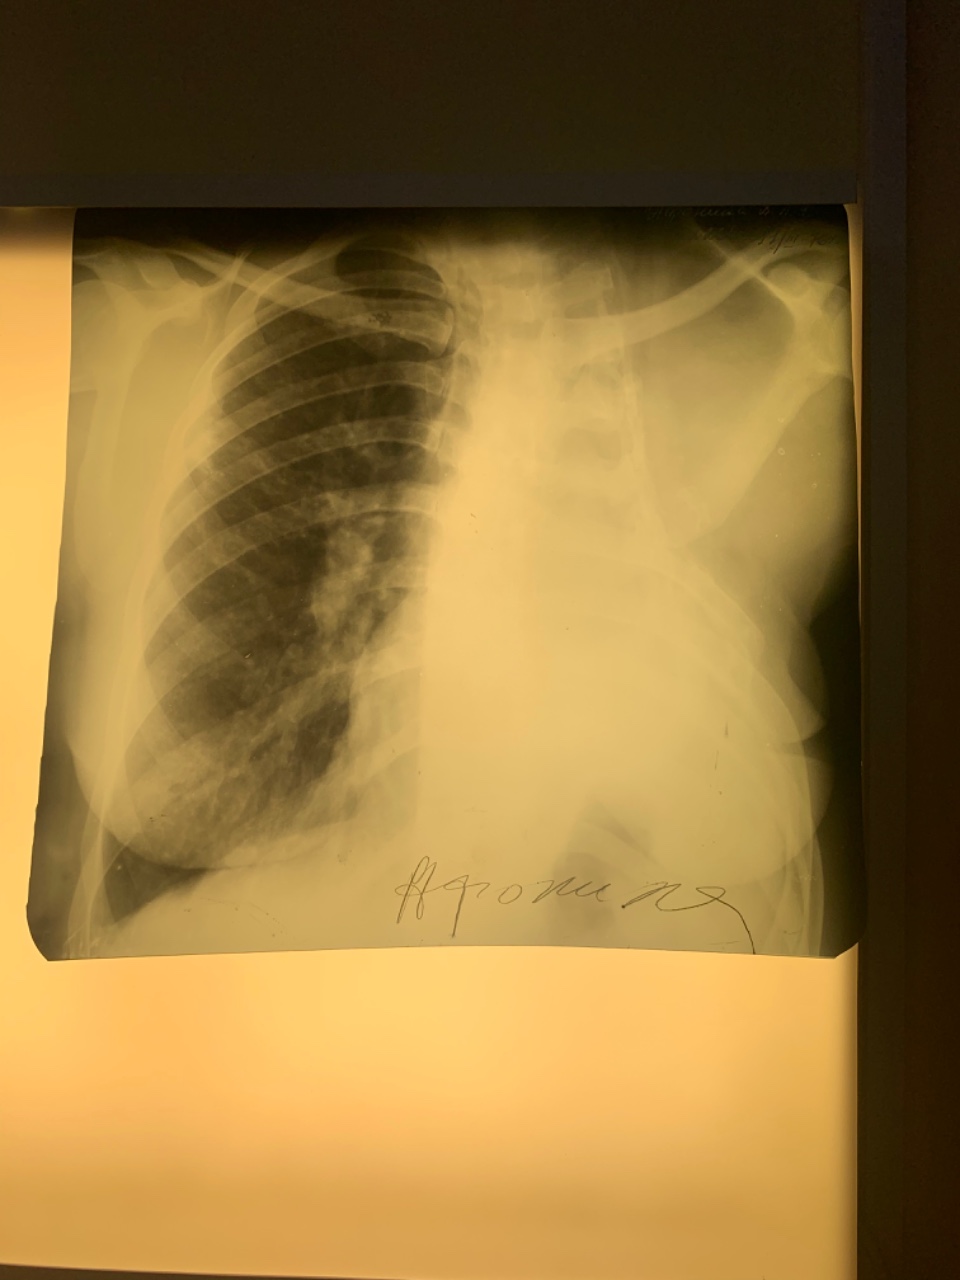

Что такое малоконтрастная рентгенограмма органов грудной клетки